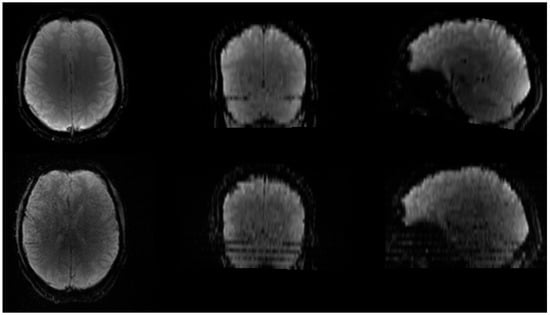

Figure 4. Subject motion causes image blurring and may lead to stripes in the phase encoding direction. Top panel is DSC acquisition without motion, bottom panel is DSC acquisition with motion.

Subject motion is a common issue in MRI scans, particularly in modalities that require dynamic image acquisitions, such as fMRI and DSC MRI. While motion can introduce artefacts (Figure 4) and affect the accuracy of perfusion measurements, the rapid EPI acquisitions allow for some correction possibilities through rigid body alignment [29,53,54]. The motion correction step ensures that any artefacts due to head movement are minimized, improving the consistency and reliability of the measurements across different scans. Prior to the application of motion correction, the first determination of motion within the data should be made. This motion determination is performed using visual inspection of both the DSC images themselves (i.e., does the brain location change during acquisition) and by plotting the time–signal–intensity curve (Figure 5). Within the time–signal–intensity curves, motion is often visualized as a sharp peak. When assessing the motion between the images, the first acquired image should be used as a reference to which the other images are compared for motion determination. If the observed motion is larger than the voxel size of the images, motion should be corrected for. If motion is smaller than the voxel size of the images, motion should not be corrected for. This is because the application of motion correction uses interpolation to reach an agreement (i.e., similar voxels in the surrounding regions). Such interpolation induces noise in the images, which may affect the parameter extraction. However, when the motion is larger than the voxel size, the motion itself introduces more noise than the interpolation, and hence, motion correction should be applied. Aside from translation, motion rotation is also important to consider. If rotational motion is smaller than the in-plane angular resolution implied by the voxel dimensions and brain size, motion correction is generally not necessary. This is because the minor angular displacement typically results in sub-voxel misalignments that do not substantially alter the spatial correspondence across time points. Correcting for such small rotations requires interpolation, which can introduce spatial smoothing and temporal noise, potentially degrading the accuracy of perfusion metrics. However, when rotational motion exceeds this threshold, causing misalignment of structures beyond the voxel size, uncorrected motion becomes a greater source of error than interpolation. In these cases, motion correction should be applied to preserve the consistency of anatomical locations over time and to ensure accurate extraction of perfusion parameters. Measurement of the motion can be performed on a very broad scale of image viewing software, like DICOM viewers or Vinci.